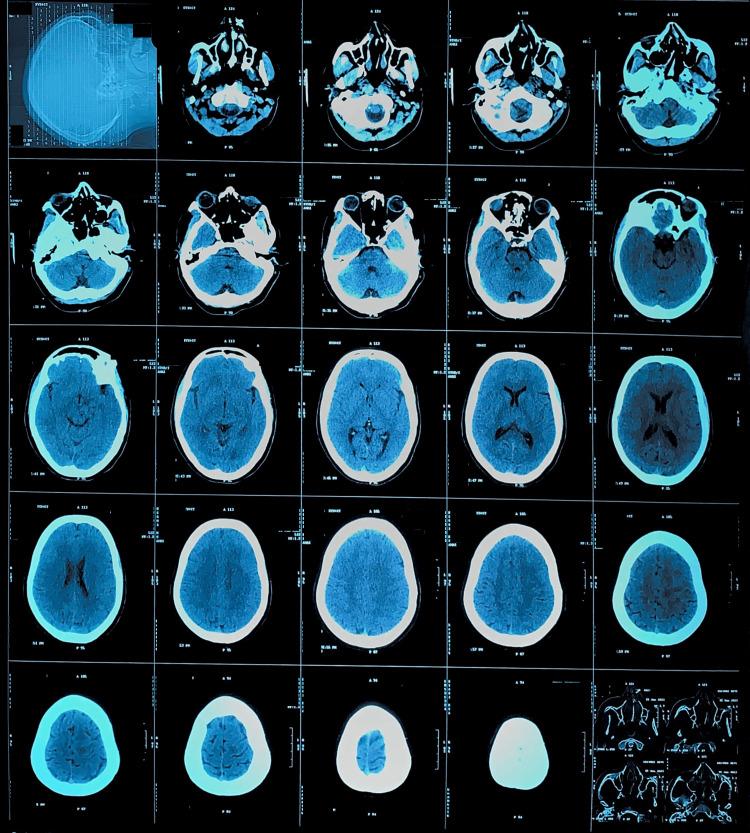

A Rare Case of Sporadic Hemiplegic Migraine Mimicking Stroke: A Diagnostic Challenge Solved by Comprehensive History Taking.

Migraine, a common affliction, manifests as debilitating headaches often accompanied by auras. However, hemiplegic migraine presents an unusual symptomatology, inducing unilateral paralysis during attacks. This condition, occurring in two forms, familial and sporadic, merits attention due to its rarity. To raise awareness of this ailment, we recount the case of a 33-year-old woman. This instance serves as a poignant reminder of the potential severity and complexity of hemiplegic migraines. By shedding light on this less-understood variant, we aim to enhance recognition and understanding within medical communities and among the general public. Additionally, emphasizing the importance of thorough history taking in identifying characteristic features, such as the presence of auras or unilateral paralysis preceding headaches, is paramount. Understanding these nuances aids in accurate diagnosis and formulation of tailored management strategies. It's imperative to recognize the distinct characteristics of hemiplegic migraines to ensure timely and appropriate management for affected individuals, offering them relief and improving their quality of life.